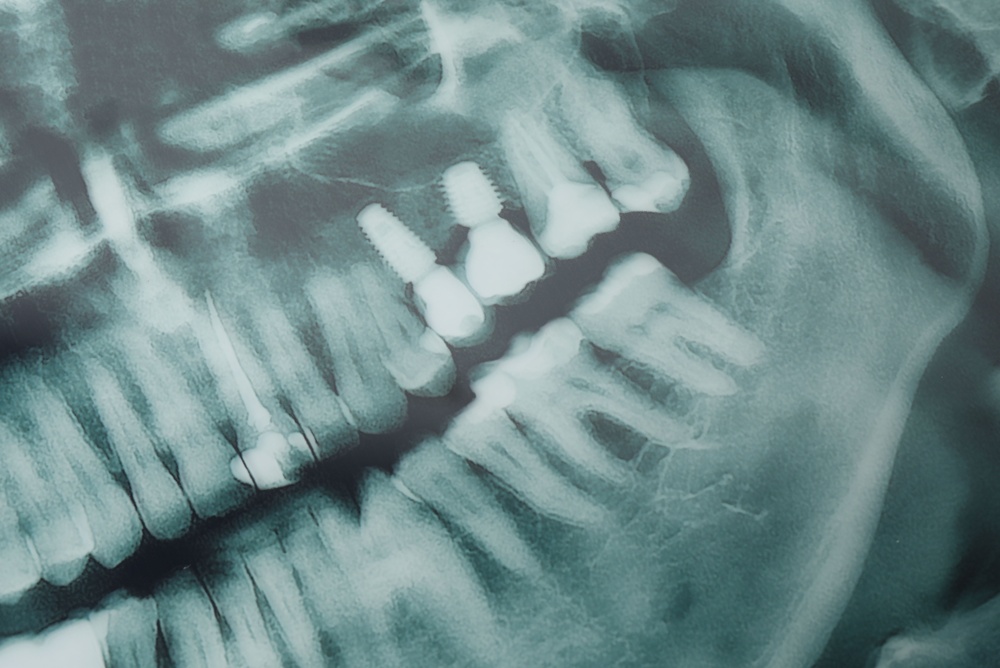

A first visit usually lasts 30–60 minutes. Your dentist reviews medical history, takes 3D scans, and discusses goals. Digital planning software creates a surgical plan and timeline. Expect questions about medications, smoking, and budget so the team can estimate your tooth implant procedure time in Thayer, MO.

A straightforward implant placement often takes 30–90 minutes per tooth. The visit includes local anesthesia (or sedation if chosen), precise drilling, implant insertion, and suturing. Simple cases are faster; teeth with tight spaces or complex anatomy may take longer. Most patients are in the office for the planned time plus short check‑in/out.

Guided surgery, intraoral scanning, and in‑house labs cut chair time and reduce appointments. Digital scans and surgical guides make placement faster and more accurate, and same‑site labs speed crown fabrication—shrinking overall tooth implant procedure time in Thayer, MO.